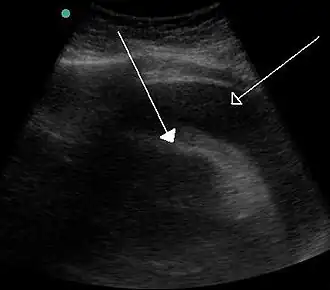

Un épanchement péricardique très important entraînant une tamponnade à la suite d'un saignement comme on le voit à l'échographie. Flèche pleine = le cœur ; flèche creuse = l'épanchement.